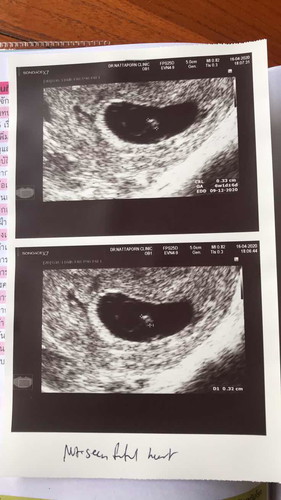

รา 9w กว่าแล้ว หมอนัดวันนี้ซาวทางช่องคลอด หมอบอกว่าไม่เห็นหัวใจเด็ก และเด็กอาจจะเสียชีวิตในท้อง หมอเล่ยให้เผื่อใจไว้บ้าง .... คุณแม่ว่าเราจะมีหวังไหม๋? อีก2อาทิตย์หมอนัดซาวอีกรอบ กังวลใจมาก ผิดหวังมาหลายรอบแล้ว ไม่สำเร็จสักที